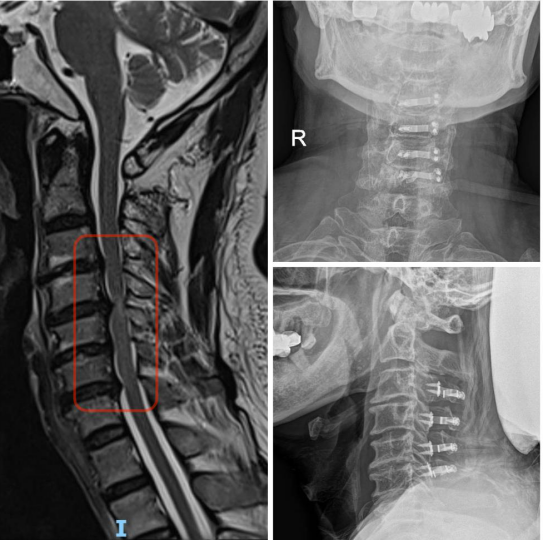

2.下颈椎

⑴颈椎前路手术:椎间盘切除Cage椎间融合术;椎体次全切椎管减压钛笼钛板内固定术。⑵颈椎后路手术:后路单开门、双开门椎管扩大成形术;侧块螺钉钉棒内固定术。⑶颈椎前后路联合手术,一期完成治疗复杂性颈椎病。

图注:手术前MRI显示多节段颈椎间盘突出、椎管狭窄、脊髓受压,手术予后路颈椎板单开门,解除脊髓受压。